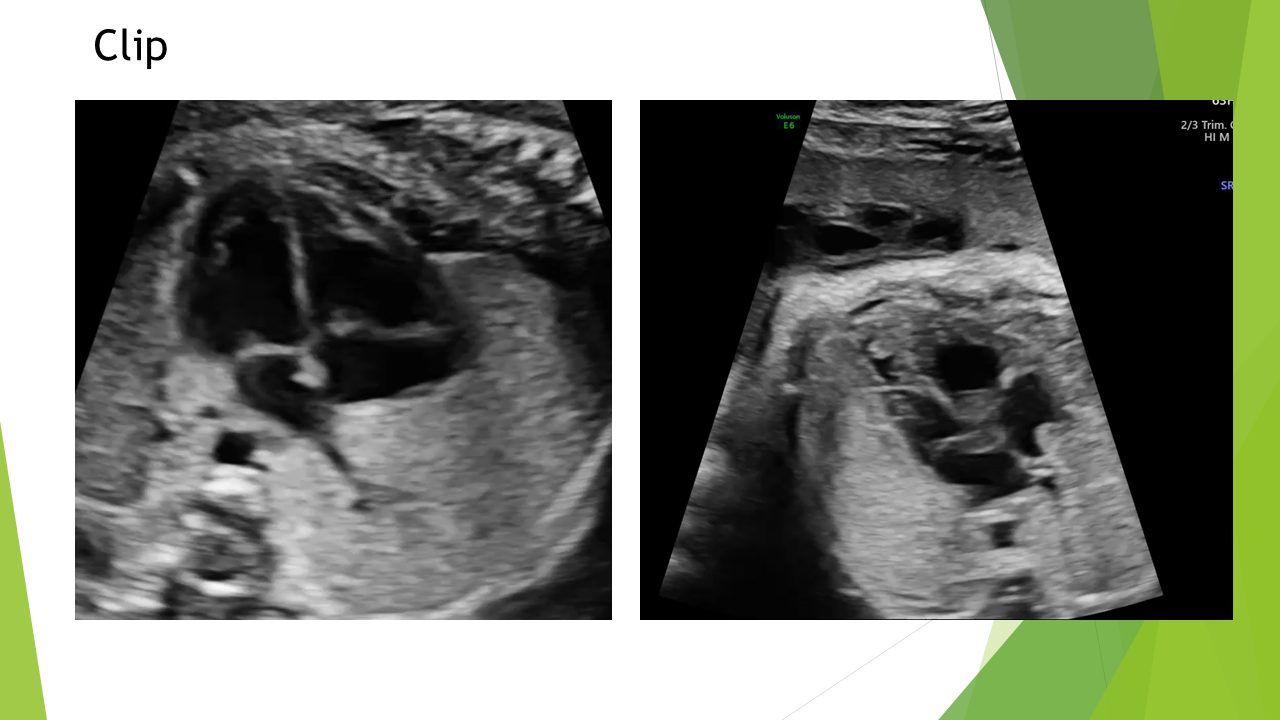

Siêu âm tim thai bằng phương pháp LEVY và STOS. 5-4-3-2-1